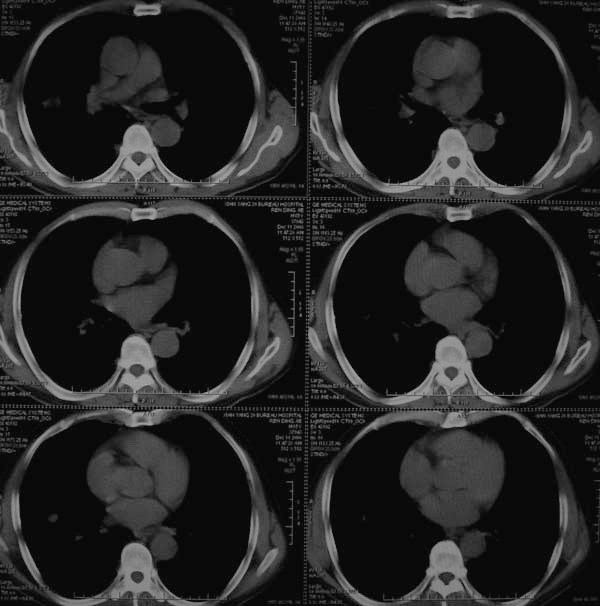

标题: CT17173:M65Y,咳嗽一月。请会诊 [打印本页]

标题: CT17173:M65Y,咳嗽一月。请会诊

右肺多发病灶,右上肺及下肺背段均有灶,考虑结核,

高度提示恶性病变(叶间裂及胸膜下可见结节),多原发或继发.建议高分辨及强化扫描.